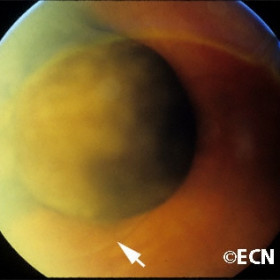

Choroidal melanoma

Collar button shaped also called "mushroom shaped" with a small associated retinal detachment (arrow).